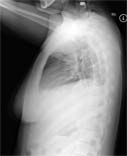

Lateral chest on a normal female.